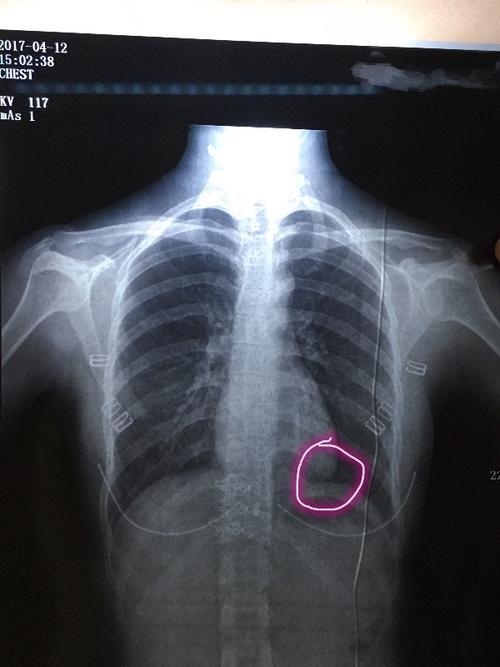

胸片入门攻略,看完不信你还学不会!

拍摄体位 正位胸片-后前位 床旁x片-前后位 1.纵膈增宽 2.心影增大 3.

读完此文,终于学会看胸片了

气胸x线胸片图解